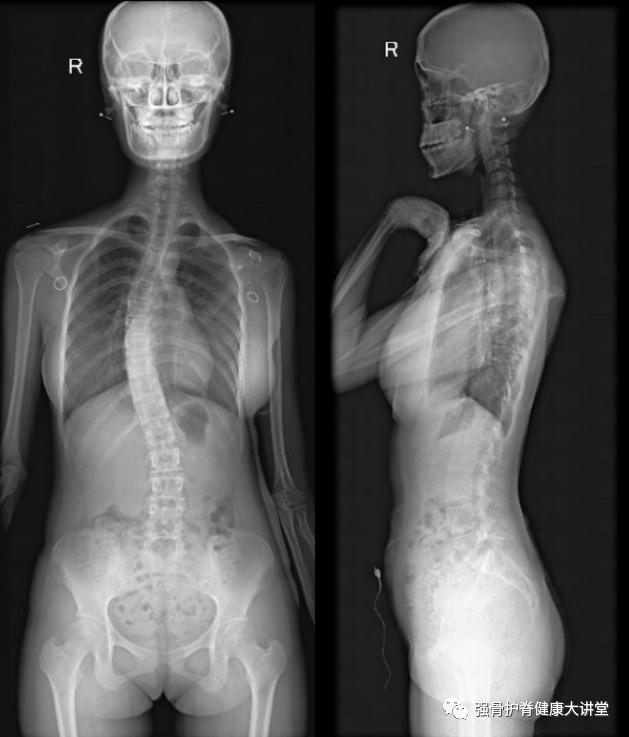

治疗前患者影像

治疗后患者影像

治疗前胸弯36.8°,治疗后胸弯28.7°。

该患者是一名来月经4年的青少年特发性脊柱侧凸病例,Risser征4级,胸弯约36.8°,腰弯约18°。骨骼生长潜能较小,与患者父母充分沟通病情。江晓兵教授考虑该患者仍处在生长发育末期,侧凸角度在36°左右,建议先行保守治疗,予支具+运动疗法+理筋正骨手法系统治疗。家长在了解到本团队举办侧弯训练营专为侧弯患儿订制个性化治疗方案后,积极为孩子报名。通过积极参加侧弯培训营,日常坚持脊柱侧凸特定动作训练,加强腰背部肌肉锻炼。7个月后复查脊柱侧得到一定程度改善,身高也有所增加,家长和患儿对治疗效果满意。